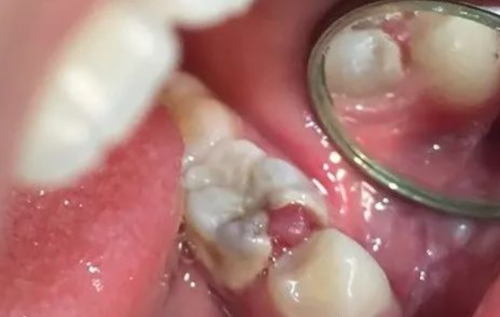

图2:冠状面看位于囊肿上方和颊侧(一般偏舌侧)

下牙槽神经被提起后,骨板上的凹槽显露出来。进一步对CT图像进行检查,确认下颌神经从颊侧骨板穿出,并且在神经与囊肿之间存在正常骨质,下颌神经在一个开放的通道内自由移动。

关于下牙槽神经的走向,已有众多解剖学和影像学研究。在大多数情况下,下颌神经位于阻生第三磨牙下方,且其与牙齿的位置关系通常在颊舌方向上变化。Maegawa等人发现,74%的下颌神经在下颌第三磨牙下方和舌侧运行。本案例中,下颌神经在第三磨牙上方和颊侧的位置非常罕见。我们认为这是第一个临床与放射学关联的外露下颌神经报告(图2、图3)。目前文献中尚无相关变异发生率的信息。